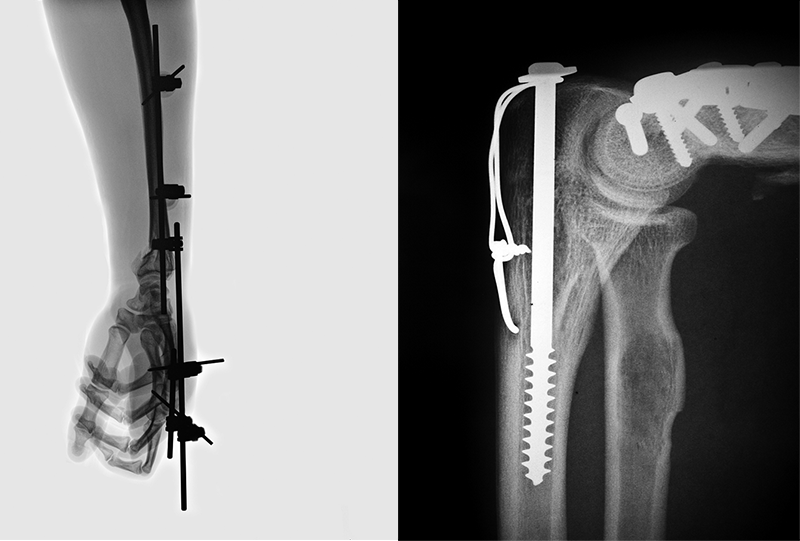

三、临床实例:协同高科陶瓷3D打印机的“精准修复”实践

在某三甲医院的颌面骨缺损修复案例中,协同高科的陶瓷3D打印机展现了强大的临床价值:一名因颌面骨肿瘤接受切除手术的患者,需要定制一款与缺损区域完全适配的植入体,以恢复面部形态与咀嚼功能。

医疗团队先通过CT扫描获取患者颌面骨缺损区域的三维数据,随后与协同高科技术团队合作,利用专业软件完成植入体模型设计——模型不仅还原了缺损区域的轮廓,还模拟了自然骨小梁的多孔结构,以促进术后骨融合。设计完成后,协同高科的XT-C200陶瓷3D打印机严格按照陶瓷3D打印机标准流程,采用TCP生物陶瓷浆料进行打印,仅用3天就完成了植入体制造,相比传统工艺的2周周期大幅缩短。

术后6个月随访显示,患者植入体与自身骨组织融合良好,面部形态恢复自然,咀嚼功能也逐步恢复至术前水平,未出现任何排异或松动问题。这一案例不仅验证了陶瓷3D打印机在定制骨植入体临床应用中的可靠性,更凸显了协同高科作为设备提供商的技术实力——其自主可控的设备与材料体系,能为临床提供“从设计到交付”的全流程保障。